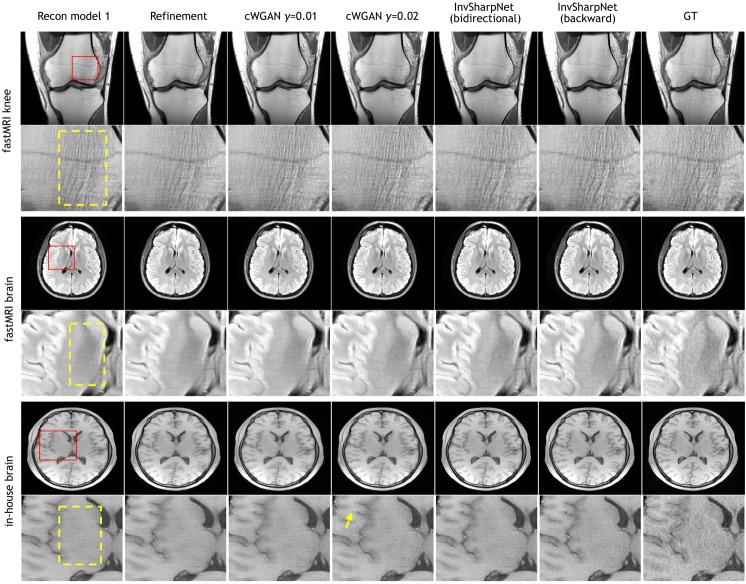

Refer to caption

Figure 2: Qualitative comparisons. The red boxes indicate the zoom-in areas and the yellow dashed boxes show regions where sharpness difference can be observed. The yellow arrow is an example of artifacts introduced by cWGAN. GT = Ground Truth.

Qualitative Measure Fig.2 illustrates examples of the sharpening results given by the compared methods on both public fastMRI and in-house datasets. The first column shows that the reconstructions given by recon model 1 look blurry compared to the ground truth images in the last column. As shown in the second column, training a refinement network in the forward direction produces almost identical images to the original reconstructions and fails to improve the visual quality. As well-documented in previous literature, training with the adversarial loss (cWGAN γ=0.01𝛾0.01\gamma=0.01) can improve the image sharpness, and using a stronger weight (γ=0.02𝛾0.02\gamma=0.02) can achieve further improvement. Using InvSharpNet with bidirectional training achieved a similar level of sharpness enhancement as using cWGAN γ=0.01𝛾0.01\gamma=0.01. Finally, using InvSharpNet with backward training achieved even better sharpness than the bidirectional training. To better understand the visual quality improvement, we provide visualizations of k-space and image profile in Appendix Fig.A1. We also show a pathology case in Appendix Fig.A2.

The main advantage of using InvSharpNet instead of the cWGAN is the lower risk of introducing artifacts. As shown in Fig.2 and Appendix Fig.A3, using generative models like cWGAN introduces artifacts (indicated by the yellow arrows) that were neither originally contained in the reconstructions nor contained in the ground truth, increasing the risk of incorrect medical diagnosis. Additionally, our results were evaluated from a clinical perspective using radiologists’ ratings, which was considered as a key evaluation criterion in fastMRI competitions [9, 14]. 2 radiologists examined the image quality of 6 selected cases (156 2D images) from the fastMRI knee and brain datasets in a blind fashion. The fully sampled images are given as rating references. The radiologists rated each image by artifacts, sharpness, contrast-to-noise ratio, diagnostic confidence and an overall score. The results are reported in Table 1, which shows that InvSharpNet with backward training outperforms other methods from all aspects. Although cWGAN models can also give higher sharpness scores than original reconstructions, they introduce artifacts that result in lower artifacts scores.